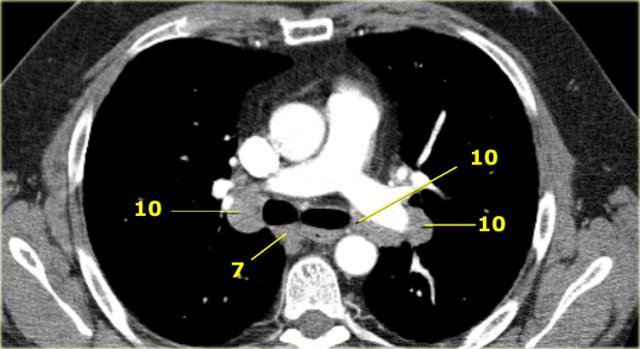

Hilar, Lobar and (sub)segmental Nodes 10-14

These are all N1-nodes.

10. Hilar nodes

These include nodes adjacent to the main stem bronchus and hilar vessels.

On the right they extend from the lower rim of the azygos vein to the interlobar region.

On the left from the upper rim of the pulmonary artery to the interlobar region.

10 Hilar nodes

Hilar nodes are proximal lobar nodes, distal to the mediastinal pleural reflection and nodes adjacent to the intermediate bronchus on the right.

Nodes in station 10 - 14 are all N1-nodes, since they are not located in the mediastinum.